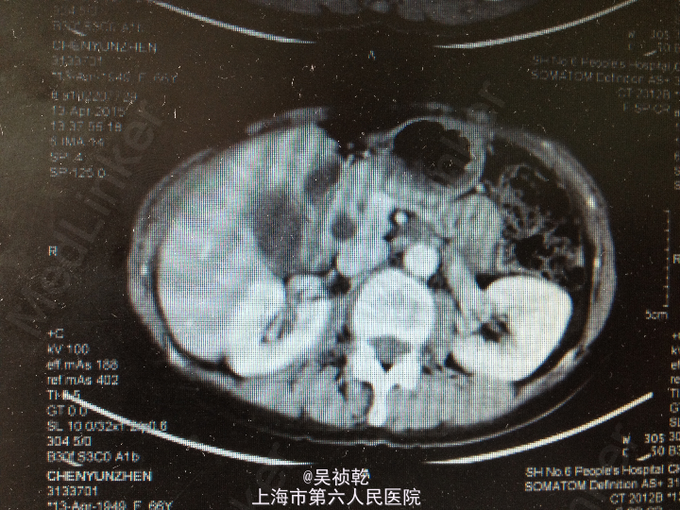

查体:皮肤巩膜无明显黄染,腹部平坦,未见明显胃肠型及异常隆起,全腹软,右上腹部压痛不明显,无反跳痛,无肌卫,无腹部反跳痛,全腹无包块,肝脏肋下未触及,脾脏肋下未触及,无肝区叩击痛,Murphy’s征阴性,肠鸣音正常,移动性浊音-。 辅查:血常规(2015-4-1):WBC:5.9×109/L,N:57.6%,RBC:4.17×1012/L,Hb:127g/L,PLT:196×109/L。肝功能:ALT:109U/L,AST:87U/L,TB:18.6umol/L。肿瘤标记物:AFP:2.7ug/L,CEA:4.71ug/L,CA19-9:37.19KU/L。 2015-4-13 上腹部MRI报告:1.胆总管下段异常信号,胆总管、胰管轻度扩张,胆总管下段结石可能大,必要时MRI增强检查,排除胆总管下段占位。2.胆囊颈结石,胆囊增大。3.附见;肝脏左叶囊性病灶。 2015-4-14上腹部增强CT报告:1.胆总管下端异常强化,结石可能,肝内外胆管及主胰管扩张,胆囊增大,必要时MRI增强进一步检查。2.肝脏小囊肿。

1. 患者入院后于4.13无明显诱因下出现右上腹疼痛,压痛明显,拒按。结合腹部CT及MRI影像学表现,胰胆管明显扩张,考虑急性胰腺炎发作。辅查:2015-4-14 生化检验报告:淀粉酶(干式) 1640 U/L ↑。生化检验报告:总蛋白 61 g/L ,白蛋白 36 g/L ,白/球比例 1.4 ,谷丙转氨酶 218 U/L ↑,谷草转氨酶 183 U/L ↑,γ-谷氨酰酶 548 U/L ↑,总胆红素 13.3 μmol/L ,直接胆红素 5.4 μmol/L ,肌酐 66 μmol/L ,血清钾 4.3 mmol/L ,血清钠 142 mmol/L ,血清氯 106 mmol/L ↑。门诊化验检验报告:白细胞 6.3 *10^9/L ,红细胞 3.84 X10^12/L ,血红蛋白 117 g/L ,细胞比积 35.9 % ,血小板 197 X10^9/L ,中性细胞百分比 58.7 % 。甲胎蛋白(AFP) 2.68 ng/mL ,癌胚抗原(CEA) 4.99 ng/mL ,糖类抗原(CA125) 6.91 U/mL ,糖类抗原(CA199) 39.45 U/mL ↑。处理:予禁食,查血、尿淀粉酶,抑酸、保肝、补液支持治疗,经治疗后症状缓解。 2. 因患者无黄疸,为进一步明确胆总管梗阻原因,4.16 行ERCP+ERBD+十二指肠乳头活检术。 检查治疗经过:十二指肠镜进入十二指肠,降部内侧见乳头,十二指肠乳头肿大,粘膜面外观正常,触之易出血。BOSTON-Jagwire导丝留置胰管,BOSTON-Jagwire导丝进入胆管引导COOK-FS-OMNI导管造影,胆管显影,胆管扩张,胰管造影胰管扩张。胆管胰管内未见充盈缺损。十二指肠乳头开口处取四块活检。放置辛菖猪胆道引流管(8.5F,6cm),辛菖胰管引流(F5,4cm),引流畅。结合MRI及CT考虑壶腹部占位可能。十二指肠乳头活检病理:绒毛状腺瘤伴部分腺体重度不典型增生,局灶癌变。 3. 患者术前诊断为十二指肠壶腹部癌,于4.23 行剖腹探查,胰十二指肠切除术。术中见:见腹腔内无腹水,腹膜、盆腔内、大网膜、肝脏、肝十二指肠韧带、胰腺周围、腹腔动脉周围、肠系膜根部、腹主动脉旁等无转移性结节和肿大淋巴结。探查见此患者左右肝胆管的汇合处接近胆胰管汇合处,右侧肝胆管壁水肿增粗,十二指肠乳头部肿块大小0.3cm,行胰十二指肠完整切除。 4. 术后病理检查报告:下半胃、胰腺、十二指肠;标本类型:切除胰腺大小 4×4×1 CM,十二指肠长 15CM,胃小弯长 8 CM,大弯长 11CM,胆囊9×3×1.5CM;肿瘤部位:肿瘤位于十二指肠乳头,大小0.5×0.3CM;组织学类型内容: 腺癌II级;血管浸润(-),淋巴管浸润(-),神经周围浸润(-);切缘: 上、下切缘及胰腺切缘均未见癌;淋巴结:以下淋巴结均未见癌转移:胰腺旁LN:0/8枚,胃大弯LN:0/6枚,胃小弯LN:0/3枚。;淋巴结免疫反应状态: SH(+), PH(+), GH(+);肿瘤旁病变: 粘膜组织慢性炎(十二指肠乳头):腺癌II级,肿瘤侵及肌层,未累及胰腺,胰腺导管扩张,小胆管增生伴中度不典型增生。(胆囊):慢性胆囊炎伴腺体增生。肿瘤组织免疫酶标记结果:CA199(-)、CEA(+)、S-100(-)、CK19(+)、CK7(+)、CDX2(-)、CK(-)、Ki67(80%+)。